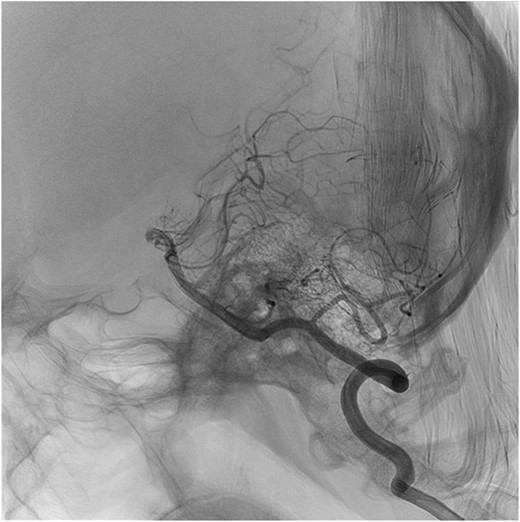

During post-operative day 1, the patient experienced paresthesias in upper and lower extremities, motor weakness (0/5 in bilateral lower extremities and 2/5 in the left upper extremity), loss of bladder sensation and urinary retention requiring a foley catheter insertion. Neurology team assessed the patient, diagnosing an anterior spinal cord syndrome. Chin stitches were removed and neck flexion was reduced to 30°, and an emergent cervico-thoracic spine magnetic resonance was performed to evaluate vascular damage. T2 and STIR sequences showed cervical kyphosis and two hyperintense lesions in the ventral spinal cord at the level of C4–C5, and the gray matter of C6–C7 (Fig. 1). Posteriorly, a brain angiogram was performed to rule out arterial occlusions with no suggestive findings of artery damage (Fig. 2).

Sagittal cut of cerebral panangiography showing permeability of vertebral arteries.

Compromise of anterior spinal artery results in upper motor neuron signs, loss of pain and temperature sensation, bladder and bowel dysfunction [5]. This patient had a kyphotic cervical spine because of previous head trauma. Given the large tracheal resection, post-operative care demands neck hyperflexion to prevent anastomotic dehiscence. The probable mechanism for cervical spinal cord ischemic injury was related to the neck position. After neck position was corrected, the patient’s condition started improving. Additionally, the brain angiogram ruled out the presence of occlusive vascular injuries, indicating that posture change probably restored arterial flow. It is worth mentioning that, in the absence of a brain angiogram with neck in hyperflexion, this conclusion is based on indirect evidence.